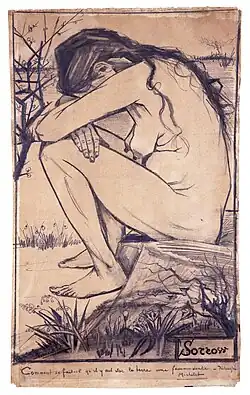

| Mesmo quando a pessoa com bulimia tem um peso saudável e normal ela continua se considerando gorda. | |